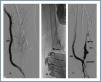

Following thrombus extraction, the most commonly occurring residual culprit lesion for thrombosis has been post-anastomotic venous stenosis for radiocephalic fistulae and stenosis of the venous anastomosis for PTFE grafts. In six cases of autologous fistulas (13.63%) and in two cases with PTFE grafts (3.57%) there was no underlying lesion (tables 4 and 5).

In 81 cases (80.2%) the thrombectomy was accompanied by angioplasty of the underlying lesion or lesions; in 14 cases (13.9%), in addition to thrombectomy and angioplasty, one or more stents was implanted; and in six cases (5.9%) thrombectomy was performed alone.

The use of stents is barely documented for cases of thrombosed dialysis arteriovenous fistulas.19-21 We have implanted them in aneurismatic dilations where manual catheter-directed aspiration was unable to extract all of the material, owing to the presence of thrombi adhering to the venous wall. These thrombi are thrombogenic in themselves, apart from the risk of coming lose and causing a pulmonary embolism. Therefore, in these cases, stents are useful as they compress them against the venous wall, and so rectify aneurisms, reduce their size and decrease risk of embolism. These stents or metal endoprostheses may or may not be coated with synthetic material, such as PTFE or Dacron. Although they are present in dialysis needle puncture zones, they are not an obstacle for them. When possible, we recommend not introducing a needle above the stent during at least two weeks.22 However, if there is not much free tract left in the skin, needles can be inserted from the moment the stent is implanted. The nursing staff’s sensation when puncturing a stent is similar to that felt when puncturing a synthetic PTFE graft. Stents may create hyperplasias at their endpoints or interior and act like stenosis; if this is detected in check-ups, they can be dilated with an angioplasty balloon to improve access permeability.

Figure 4.